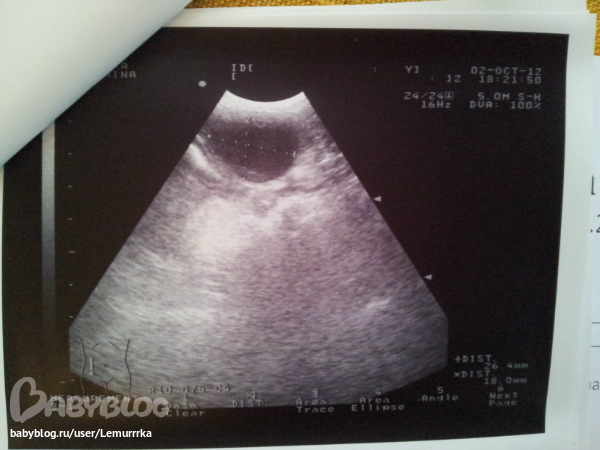

Собаки. Болезни, прививки, советы по уходуПошли вчера мы с Фаней на УЗИ. Просто так, безо всяких там жалоб, для профилактики, чтобы убедиться, что все в порядке. А нифига. Нашли кисту в матке, сказали надо удалать вместе с маткой и яичниками.... и под одним наркозом заодно и зубы почистят....

При всем при этом, результаты анализов крови нормальные.... как так?

Операция не экстренная, но необходимая, т.к. киста может рано или поздно лопнуть... дали нам на все про все месяц. Но я решила не тянуть, записалась на субботу, чтобы муж с нами тоже был. Как потом колоть ей антибиотики вообще не представляю, они же такие болючие.... по себе знаю... до сих пор вздрагиваю от одной мысли....